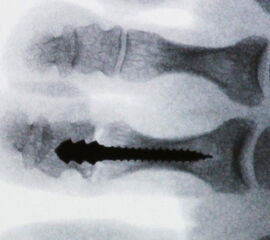

Ziel der PIP-Arthrodese ist die Aufhebung der Flexionsfehlstellung im PIP-Gelenk sowie die Erlangung einer ausreichenden mechanischen Stabilität um Rezidive bzw. Fehlstellungen zu vermeiden. Das Operationsprinzip der Korrektur basiert auf einer knöchernen Verkürzung im Bereich des PIP-Gelenkes um eine spannungslose Extension zu ermöglichen. Neben einer vollständigen Entknorpelung der Gelenkflächen wird eine postoperative Stabilisierung durchgeführt, um eine knöcherne Fusion zu erzielen. Die dazu am häufigsten verwendete Technik ist die Fixierung mittels intramedullärem Kirschner-(K-)Draht, der im Bereich der Zehenkuppe ausgeleitet und nach einigen Wochen entfernt wird. Alternative Fixationsverfahren sind die Verwendung von Mini-Schrauben oder resorbierbaren intramedullären Pins.

• Eine Röntgenkontrolle wird 6 Wochen postoperativ durchgeführt (Fuß belastet in zwei Ebenen). Besonders geachtet wird auf eine knöcherne Konsolidierung der Arthrodese und auf die Lage eines gegebenenfalls verwendeten intramedullären Implantats.